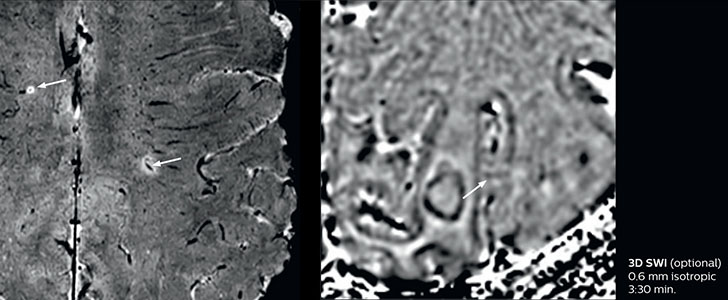

Dr. Savatovsky appreciates the improvements and flexibility that Elition with Compressed SENSE and MultiBand SENSE provides, particularly for stroke patients. “For stroke, it allows us to cut about 5 minutes off of our stroke protocol, or to keep the same acquisition time and get more insights.” The ability to perform more sequences can help in making a swift and confident diagnosis. “For example, our stroke cases usually include the regular sequences that every center does (b1000 diffusion, FLAIR, time-of-flight angiography), but we also image supra aortic vessels, and we can replace a gradient echo sequence with a fast 50-second susceptibility-weighted sequence, and all of this doesn’t add much time. because all the regular sequences are accelerated on Elition.” “The time savings with Compressed SENSE and MultiBand SENSE make it easier to add sequences to give us additional insights. Depending on the context and the first results, we might add a DSC perfusion to assess the ischemic penumbra, an ASL perfusion to help find an alternative cause in case of normal diffusion, or add a high-resolution T1 sequence for a stroke patient, to quickly assess wall imaging in emergency cases. The additional sequences can help improve patient management, because we can already consider some alternative diagnoses if the morphological MRI is normal.”

In this patient with acute right motor deficit and aphasia, the b2000 diffusion weighted image is normal. The SWIp image demonstrates more prominent veins in the right hemisphere, which could reflect increased deoxyhemoglobin contents. Fast ASL shows low CBF regions in the left frontal lobe. A follow-up ASL after one hour demonstrates high CBF values in the same area. The final diagnosis was migraine with aura.